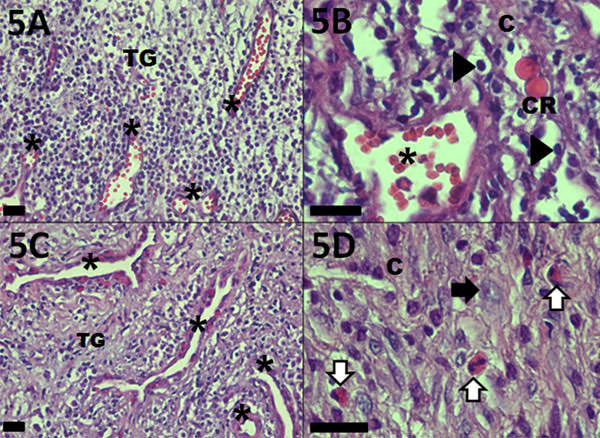

La lesión extirpada, de color rojo-marrón, superficie lisa en algunas zonas e irregular en otras, de consistencia blanda y tamaño de 15 x 15 mm (Figura 4B) fue fijada en formol al 10% y enviada para el Servicio de Patología Oral de la Universidad Federal del Río de Janeiro (Río de Janeiro, Brasil), donde fue procesada e incluida en parafina. Secciones de 5 ?m de espesor coloreadas con hematoxilina y eosina demostraron en la microscopía óptica la presencia de un tejido de granulación ricamente compuesto por vasos sanguíneos de pequeño calibre, algunas zonas de extravasación de eritrocitos, intenso infiltrado inflamatorio intersticial mononuclear (linfocitos y plasmocitos) y algunas células polimorfonucleares eosinófilos, más allá de

presencia escasa a moderada de fibroblastos, reflejando en grados variables los depósitos de colágeno de la matriz extracelular, más abundante en la periferia de la lesión. En áreas focales perivasculares se observaron cuerpos de Russell o acumulación de inmunoglobulinas por precipitación de las mismas (Figura 5A-D). Teniendo en cuenta estos hallazgos histopatológicos, el diagnóstico final fue de Granuloma Periapical.

Figura 5

Análisis histopatológico del granuloma periapical. Región central de la lesión: A - Tejido de granulación (TG) con abundantes vasos sanguíneos (*) y poco depósito de colágeno (C). B - Infiltrado inflamatorio mononuclear: linfocitos (cabezas de flecha) y plasmocitos que contienen inmunoglobulinas no segregadas o cuerpos de Russell (CR) en región perivascular (*). Periferia de la lesión: C - Tejido de granulación (TG) con abundantes vasos sanguíneos (*) y aunento de la deposición del colágeno (C). D - Eosinófilos (flechas blancas) y fibroblastos (flecha negra). Las barras de medida representan 25µm.